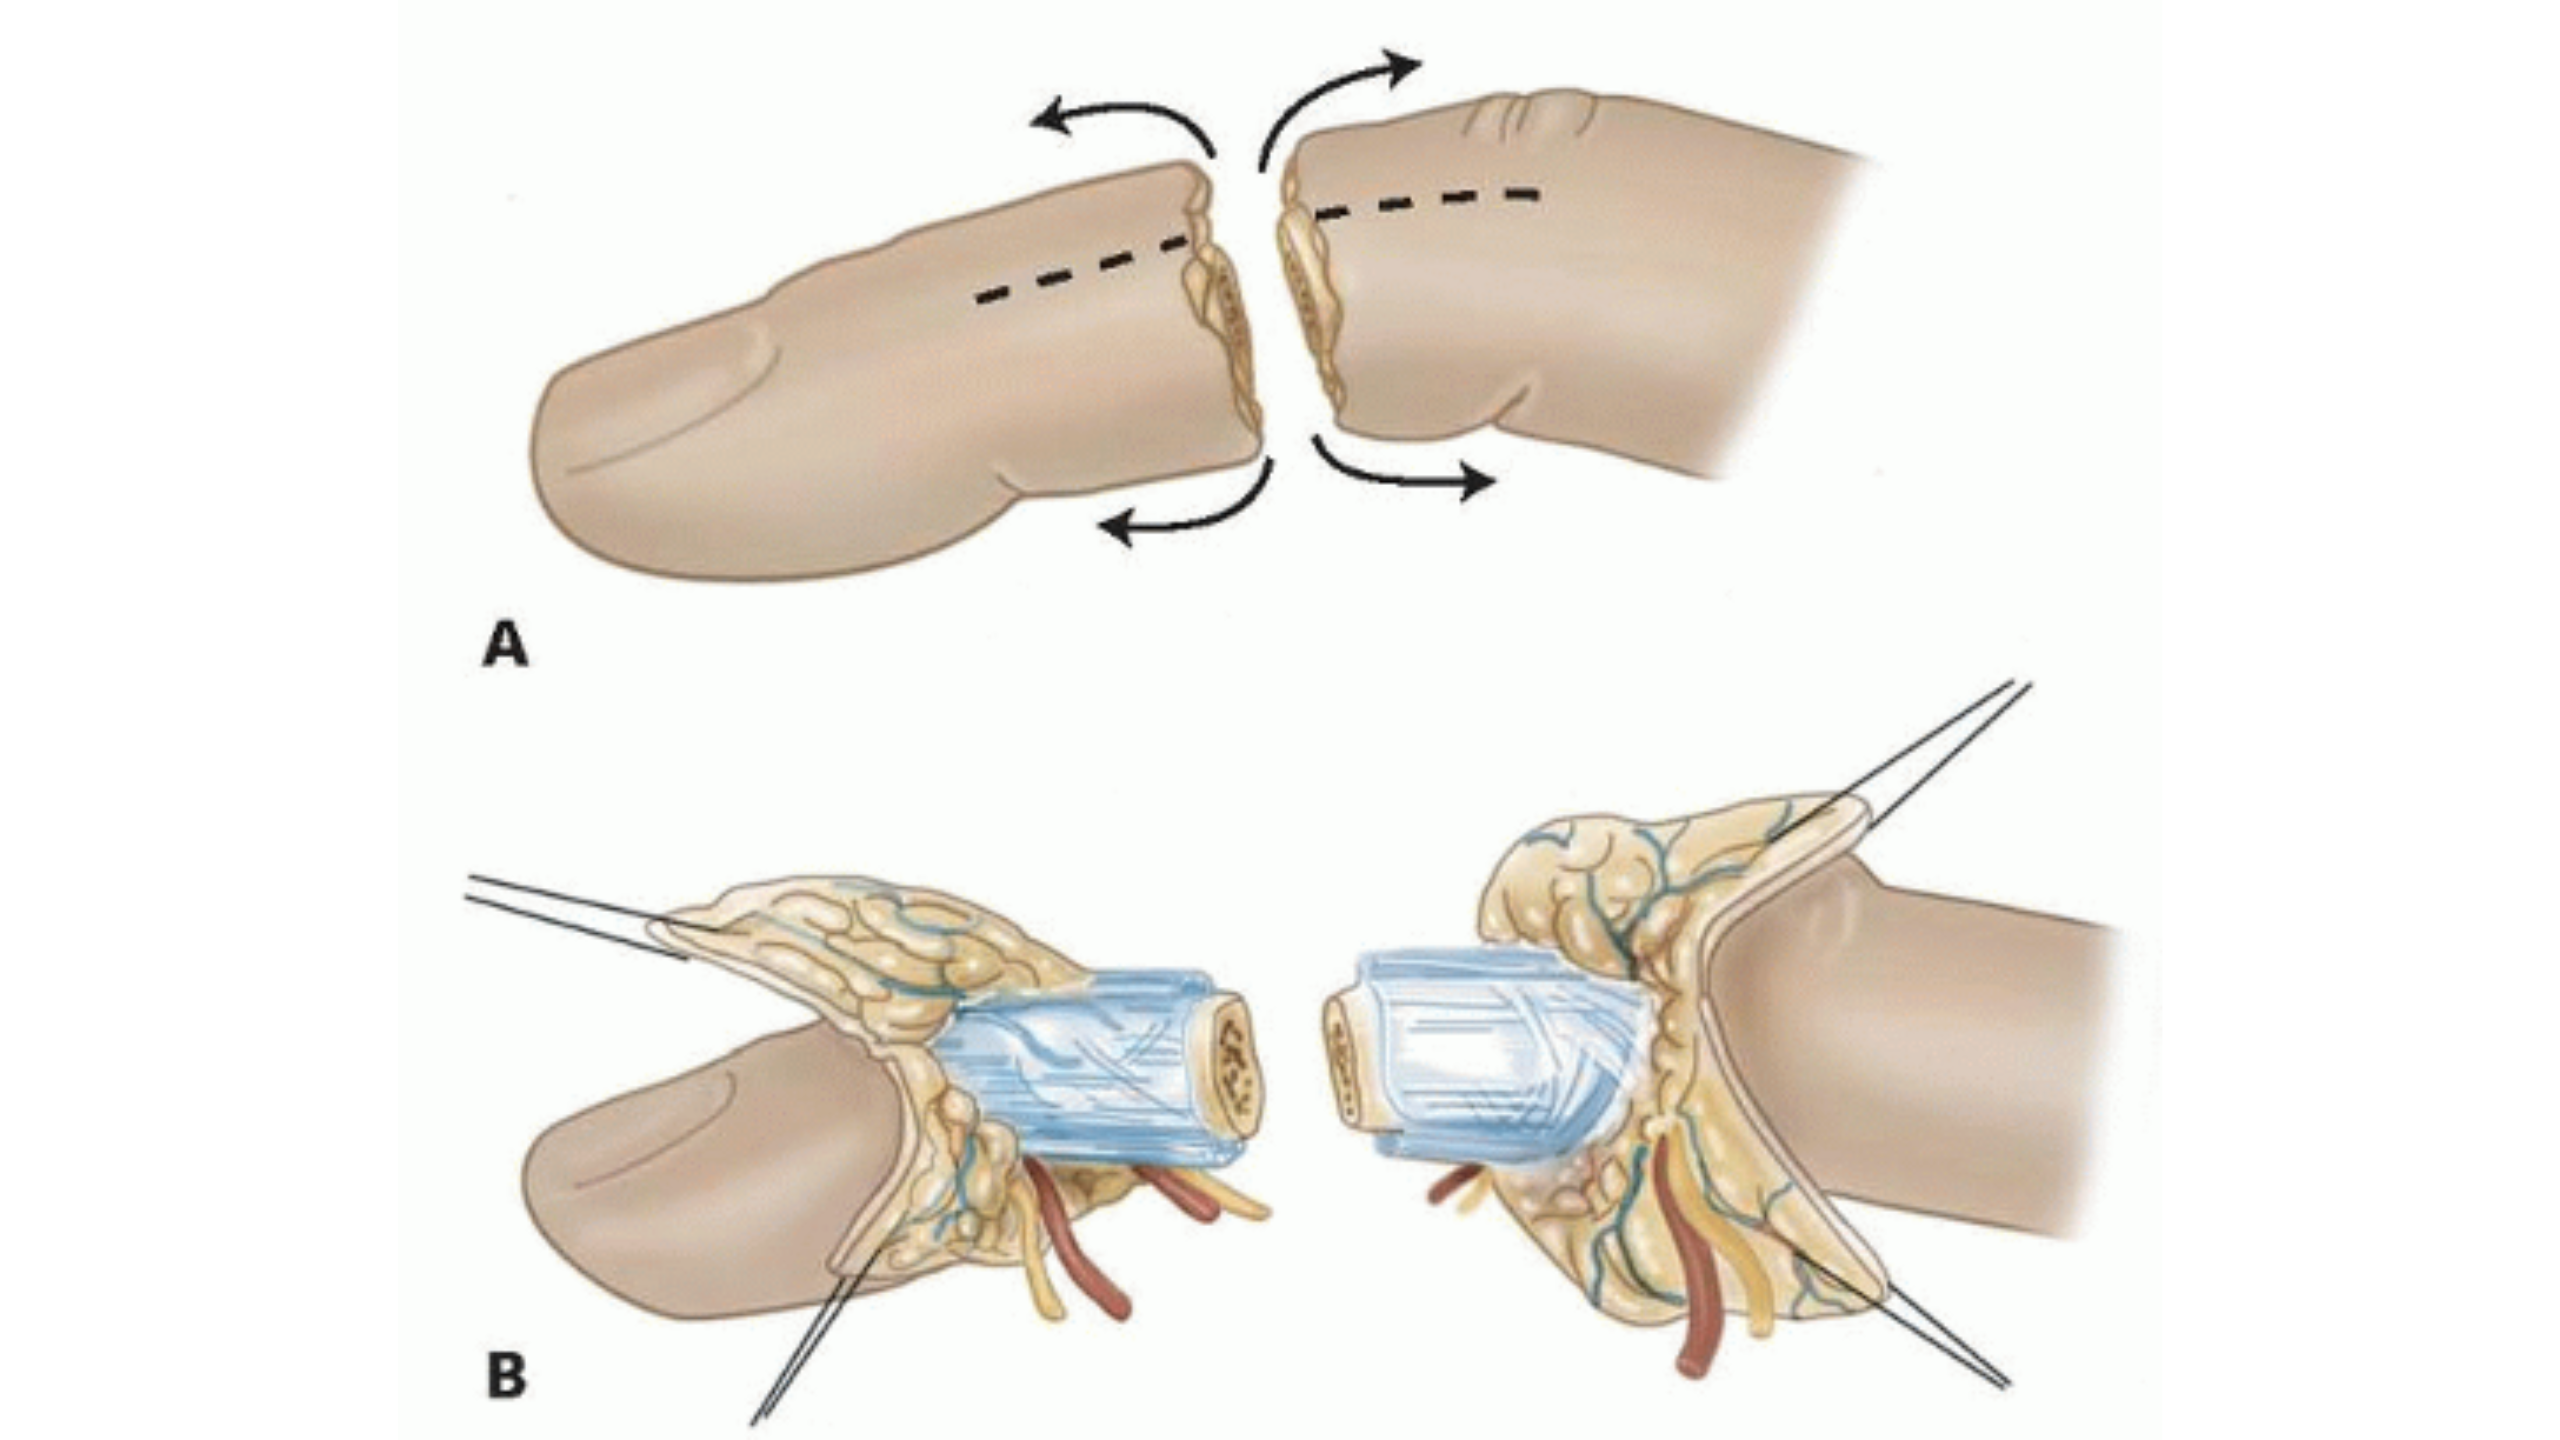

- Expert care for fractures, dislocations, and spinal injuries to restore mobility and stability.

- Rapid response for ligament tears, muscle injuries, and other sports-related trauma.